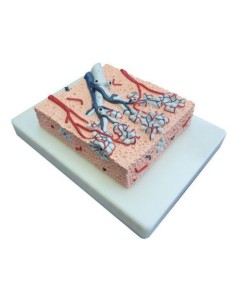

Découvrez le monde de l'anatomie avec des modèles anatomiques de précision

Bienvenue sur Tuttoanatomia.it, le portail de référence en Italie pour l'achat de modèles anatomiques, de posters, de lits portables, de simulateurs médicaux et de littérature spécialisée. Grâce à nos modèles anatomiques de pointe de 3B Scientific et Erler Zimmer, nous offrons une expérience d'apprentissage inégalée.

Des modèles anatomiques détaillés pour tous les besoins

Du crâne en 22 parties à verrouillage magnétique aux modèles de colonne vertébrale, des modèles d'articulation aux modèles de cœur, chaque pièce de notre collection est conçue pour une immersion totale dans l'étude de l'anatomie humaine. Nos modèles, réalisés à partir de scans d'os réels, garantissent une expérience tactile authentique et une fidélité de poids presque identique aux originaux.

Des outils pédagogiques innovants pour l'enseignement et la pratique de la médecine

Indispensables aux étudiants comme aux professionnels, nos modèles anatomiques sont des outils pédagogiques qui permettent d'observer les structures anatomiques avec précision, en évitant les dissections ou les études invasives. Ils sont également utiles pour expliquer les pathologies aux patients, ce qui rend la communication plus efficace et permet de gagner un temps précieux.